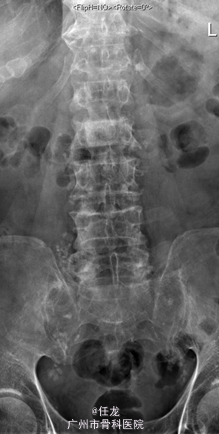

主诉:前列腺癌术后8年,反复腰痛半年,加重2周。 病史:患者8年前曾诊断为前列腺癌,并在外院行手术治疗,并多次放疗,一般坚持门诊复查。半年前出现腰部疼痛,为持续性疼痛,休息后无缓解,无双下肢麻木疼痛。最近两周加重明显,影响睡眠。遂至门诊就诊,门诊MRI考虑:前列腺癌腰椎转,故收入院作进一步诊治,患者一般情况较差。

查体:L2-L4棘突及棘旁轻度叩压痛。四肢感觉、肌力及肌张力正常。双侧坐骨神经出口处无轻压痛。双侧直腿抬高试验(-),双侧股神经牵拉试验(-)。双侧膝反射及踝反射未引出,双侧踝阵挛阴性。双侧Babinski 征及Oppenheim 征(-)。 辅助检查:PSA:73.22ng/ml ↑。腰椎影像学检查如下。

诊断:1. 前列腺癌腰椎转移 2.前列腺癌切除术后 处理:入院后完善相关检查,术前给予对症治疗,科里术前讨论决定:拟行手术:L2-4经皮穿刺活检+术中放疗+椎体成形术。